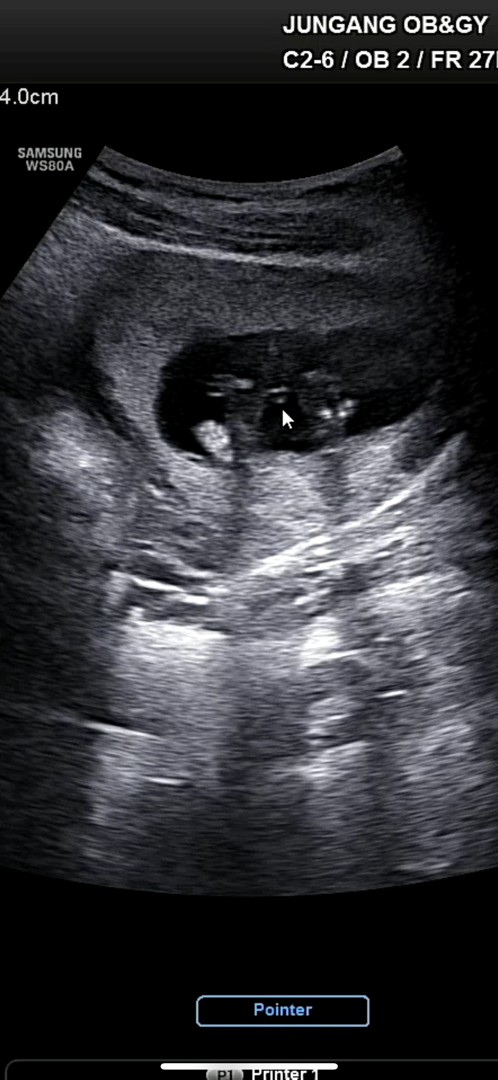

성별 봐주세여 ㅠㅠㅠ

의사선생님께서 파란옷 준비까진 아니더라도 의심해보시는게 좋을꺼같다 하셔서여

몇주인지 중요한거같은데 아들같아보여용 ㅎㅎ